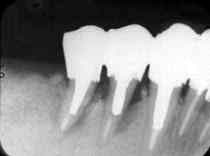

術前4年4ヵ月

術直前(1986.6)

術直後

術後3年4ヵ月

術後7年

術後10年(1995.11)

84歳(1997.4 現在)と高齢ではあるが、元気に散歩する姿を時々拝見する。 手術のおかげで義歯のお世話にならず、快適に食事ができるとのことである。